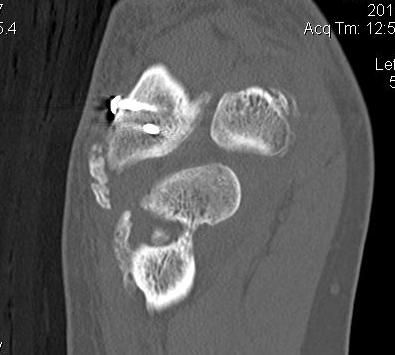

CT

Define anatomical location of the HO prior to surgical excision

- 56 elbows with post fracture HO

- 3D dimensional CT scans

- medial capsule 93%, lateral capsule 80%

- medial supracondylar 57%

- lateral supracondylar, radial head ulnar region 50%